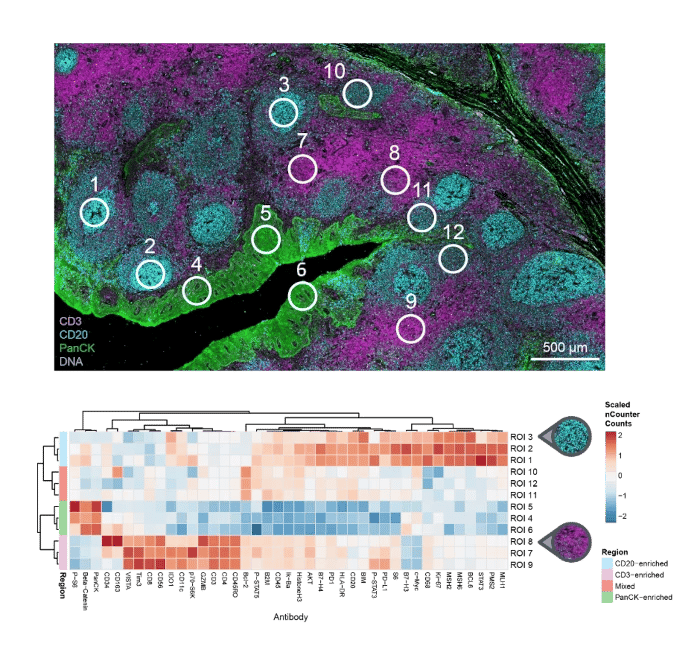

Dive into the next level of immuno-oncology research with the GeoMx IO Proteome Atlas (IPA), backed by Abcam's IHC-validated human antibodies. This leading spatial proteomics panel excels in analyzing both FFPE and fresh frozen tissue sections, opening new avenues for biomarker discovery in translational research.

The GeoMx IPA stands out by offering:

- Non-destructive profiling of over 570 proteins in various tissue areas.

- Superior data richness compared to traditional IHC or IF assays.

- Compatibility with standard histology workflows.

Take advantage of this technology to gain a deeper understanding of vital tissue microenvironments and cell types, enhancing your insights into immune responses to cancer and potential therapeutic strategies in immunology, oncology, and other research fields.